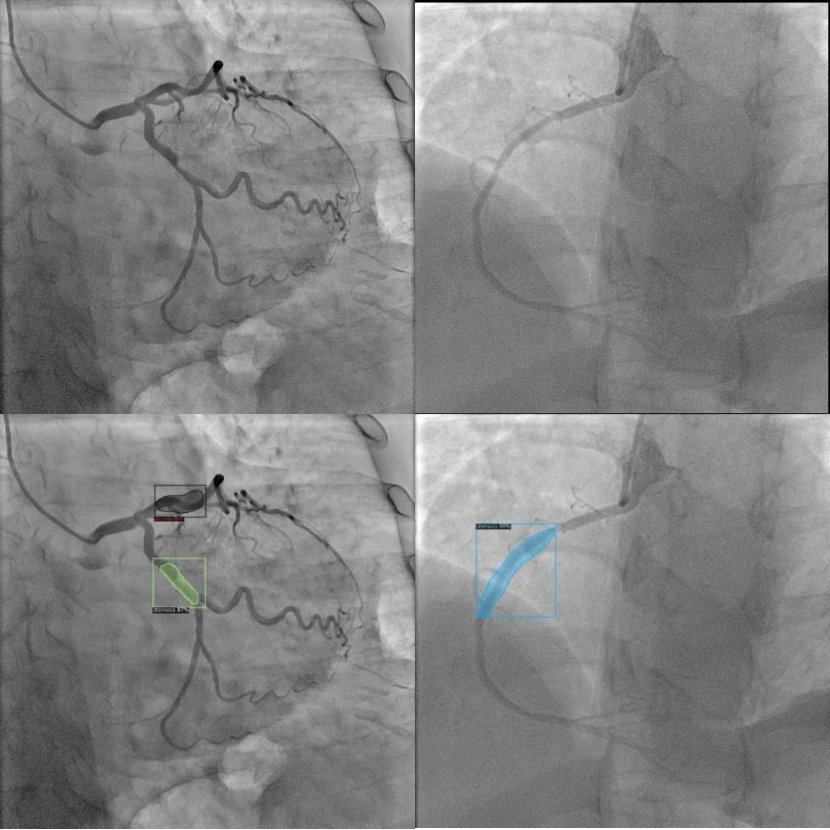

Refer to caption

Figure 4: Detection results performed on the test dataset by sample network. To the best of our knowledge, there is no model trained and tested for lesion detection on coronary vessels available for public testing and benchmarking. Top row represents the original images, and bottom row represents model response.